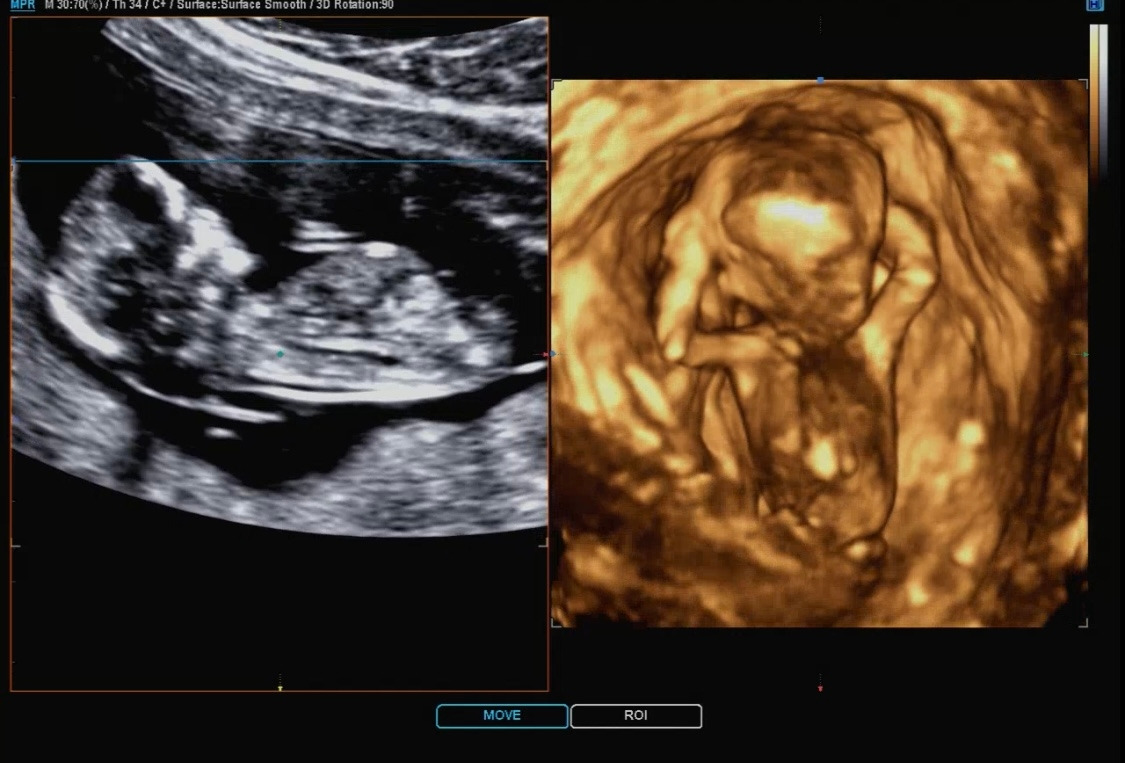

입체 초음파는 다른 건 없고 이런 식으로 아가의 모습을 입체로 바꿔서 보여주는 것을 말한다. 하지만 아직은 아가의 모습이 정확하지 않아서 처음에는 어디가 어디인지 나는 구별하기가 정말 힘들었다.

선생님께서 계속 보이시죠~ 여기가 어디고 여기가 어디예요~라고 설명해 주시는데 처음에는 전혀 모르겠더라... 그렇게 계속 보다 보니 조금씩 아가의 모습이 나도 보이기 시작했다. 12주 차의 입체 초음파는 ㅎㅎ 크게 별게 없다.

아가가 움직일 경우 순간의 스샷을 여러 개 찍어서 입체를 만드는 것이기 때문에 더 어렵다고 한다. 다올이는 계속 움직이고 자세를 바꾸는 바람에 예쁘게 입체 초음파를 찍기는 어려웠지만 선생님께서 많은 노력을 해주셨다. 입체 초음파는 4장 정도 찍어주셨다. 4장 모두 다른 모습으로 찍혔다. 하나의 포즈는 나와 똑같이 하고 있어서 선생님과 같이 엄청 웃었다.